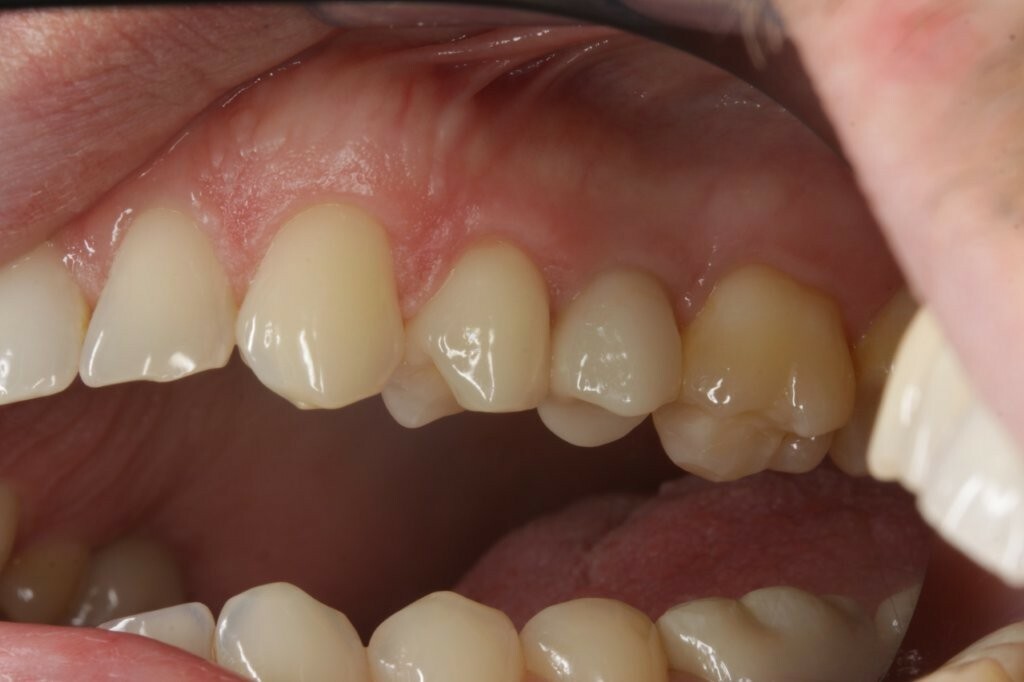

Die Hybrid-Abutmentkrone fügt sich farblich und anatomisch unauffällig in das natürliche Gebiss ein (Abb. 35+36). Auchbei der Nachkontrolle nach zweieinhalb Jahren zeigte sich eine klinisch unauffällige Versorgung, die sich harmonisch in den Zahnbogen eingliedert (Abb. 37-40).